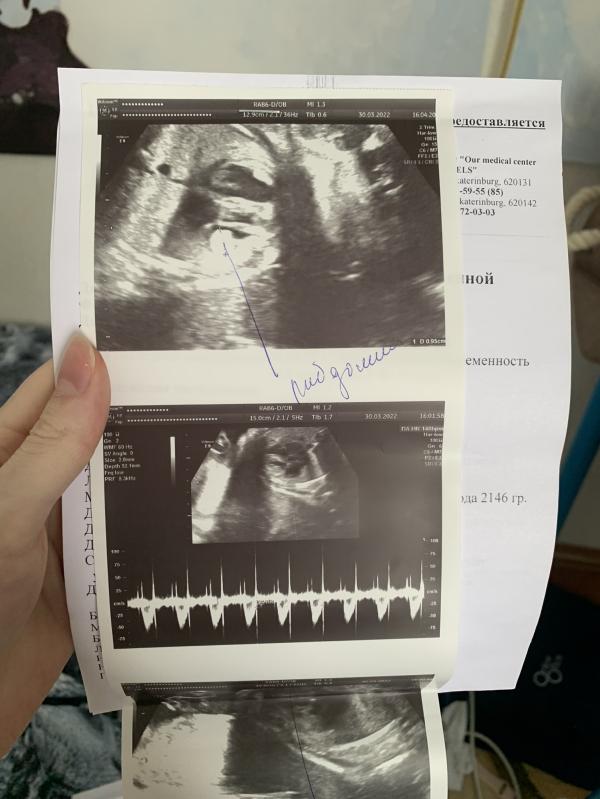

Наступило время ехать на Флотскую. Меня сразу отправили на узи, чтобы врачи убедились во всём сами. Ну и конечно же, эти чёртовы опухоли никуда не делись😭

Для того, чтобы точно подтвердился Туберозный склероз, на узи начали искать опухоли в голове у малыша. Их не нашли🙏

Но тут не понятно, либо их там действительно нет, либо по узи просто их не заметили. Тут поможет только МРТ плода, но на МРТ меня почему-то не отправили.